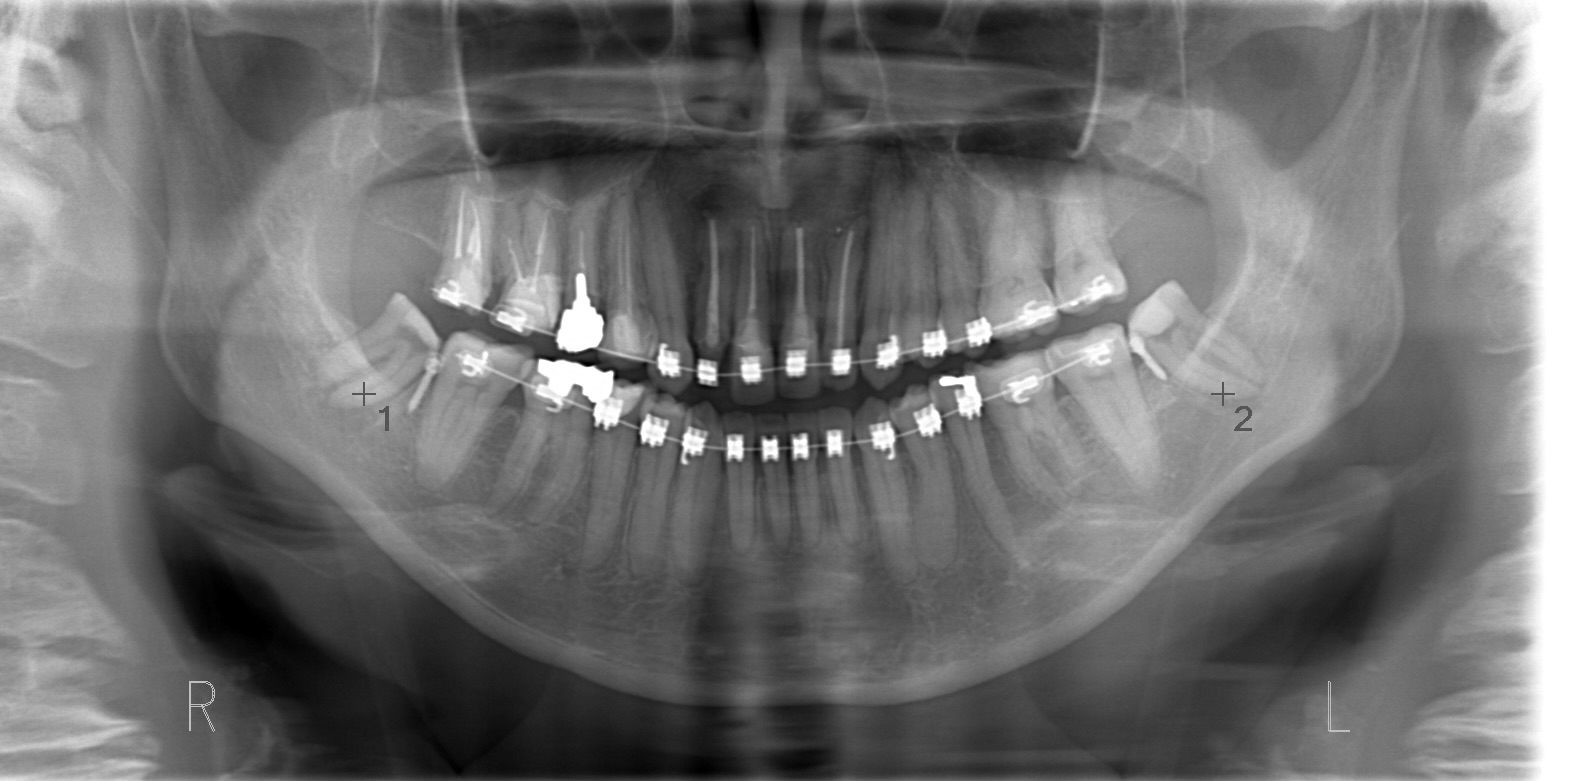

左側は噛んできたが、右側は逆の動き、つまり右側中切歯が上に上がっていってしまっている。側切歯のアンキローシス(骨癒着)を疑う。

2週間ほど側切歯の上側にワイヤーを通し周りの歯の動きを見ていると、通常であれば側切歯が下がるはずが側切歯はそのままの位置で、中切歯がより上に動いていた。よって側切歯のアンキローシストと診断する。

側切歯のブラケットを外し力をかけないようにしていると、中切歯は周りの歯に合わせて下に降りてきた。

アンキローシスを起こしている側切歯を理想的な形の仮歯に置き換え、それを周りの歯を動かしより下顎と咬合させるためのアンカーとして利用した。

オープンバイト(開口)になってしまった原因として下顎の親知らずが考えられるため、親知らずを抜歯してそのスペースに対して下顎大臼歯を圧下させたいが、親知らずが下歯槽管神経に近接しているため、すぐに抜歯することができず、親知らずの歯冠を削って少しずつ上に上がってくるのを待つ。

CT画像より親知らずが下歯槽管神経から十分離れたことを確認して抜歯を行う。